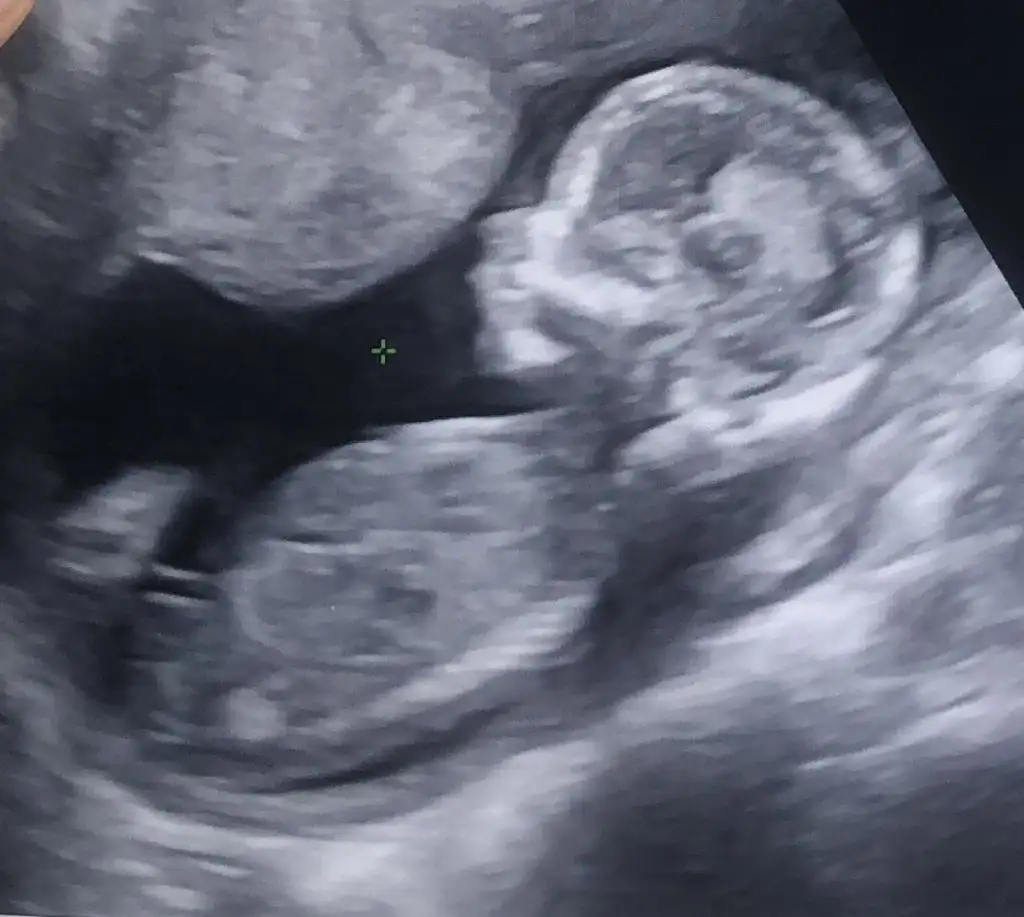

Tam emin değilim ama erkeği anımsatıyor. Çok belli değil nub kısmıMerhabalarbizde bi tahmin alabilir miyiz lütfen

Erkek11+2yim bugün kızlar doktora gittim çok şükür iyi durumumuz ve de çok hareketli maşallah sizce cinsiyeti ne tahmini olan var mı?

Bebiş oturur pozisyonda o yüzden belli olmamıştırbana da tahmin yapar mısınız burda nub a göre kız demislerdi ilk usg fotoğrafı için 15. haftada doktor %60 erkek ama 1ay sonra bı daha bakalım dedi. 18inde detaylım var o zaman net belli olur ama sanki kız gibi geliyor bana karın şeklimden. ilk gebeligimde karnım alttan sivriydi oğlum var bunda karnım yuvarlar büyüyor bilemedim. çok göstermedi cinsiyet dr karnımı salladı falan 3-5dk ugrastı görmek icin %60 erkek ama belli değil diğer ay bakarız bıdaha dedi bilemedim valla siz ne diyorsunuzz